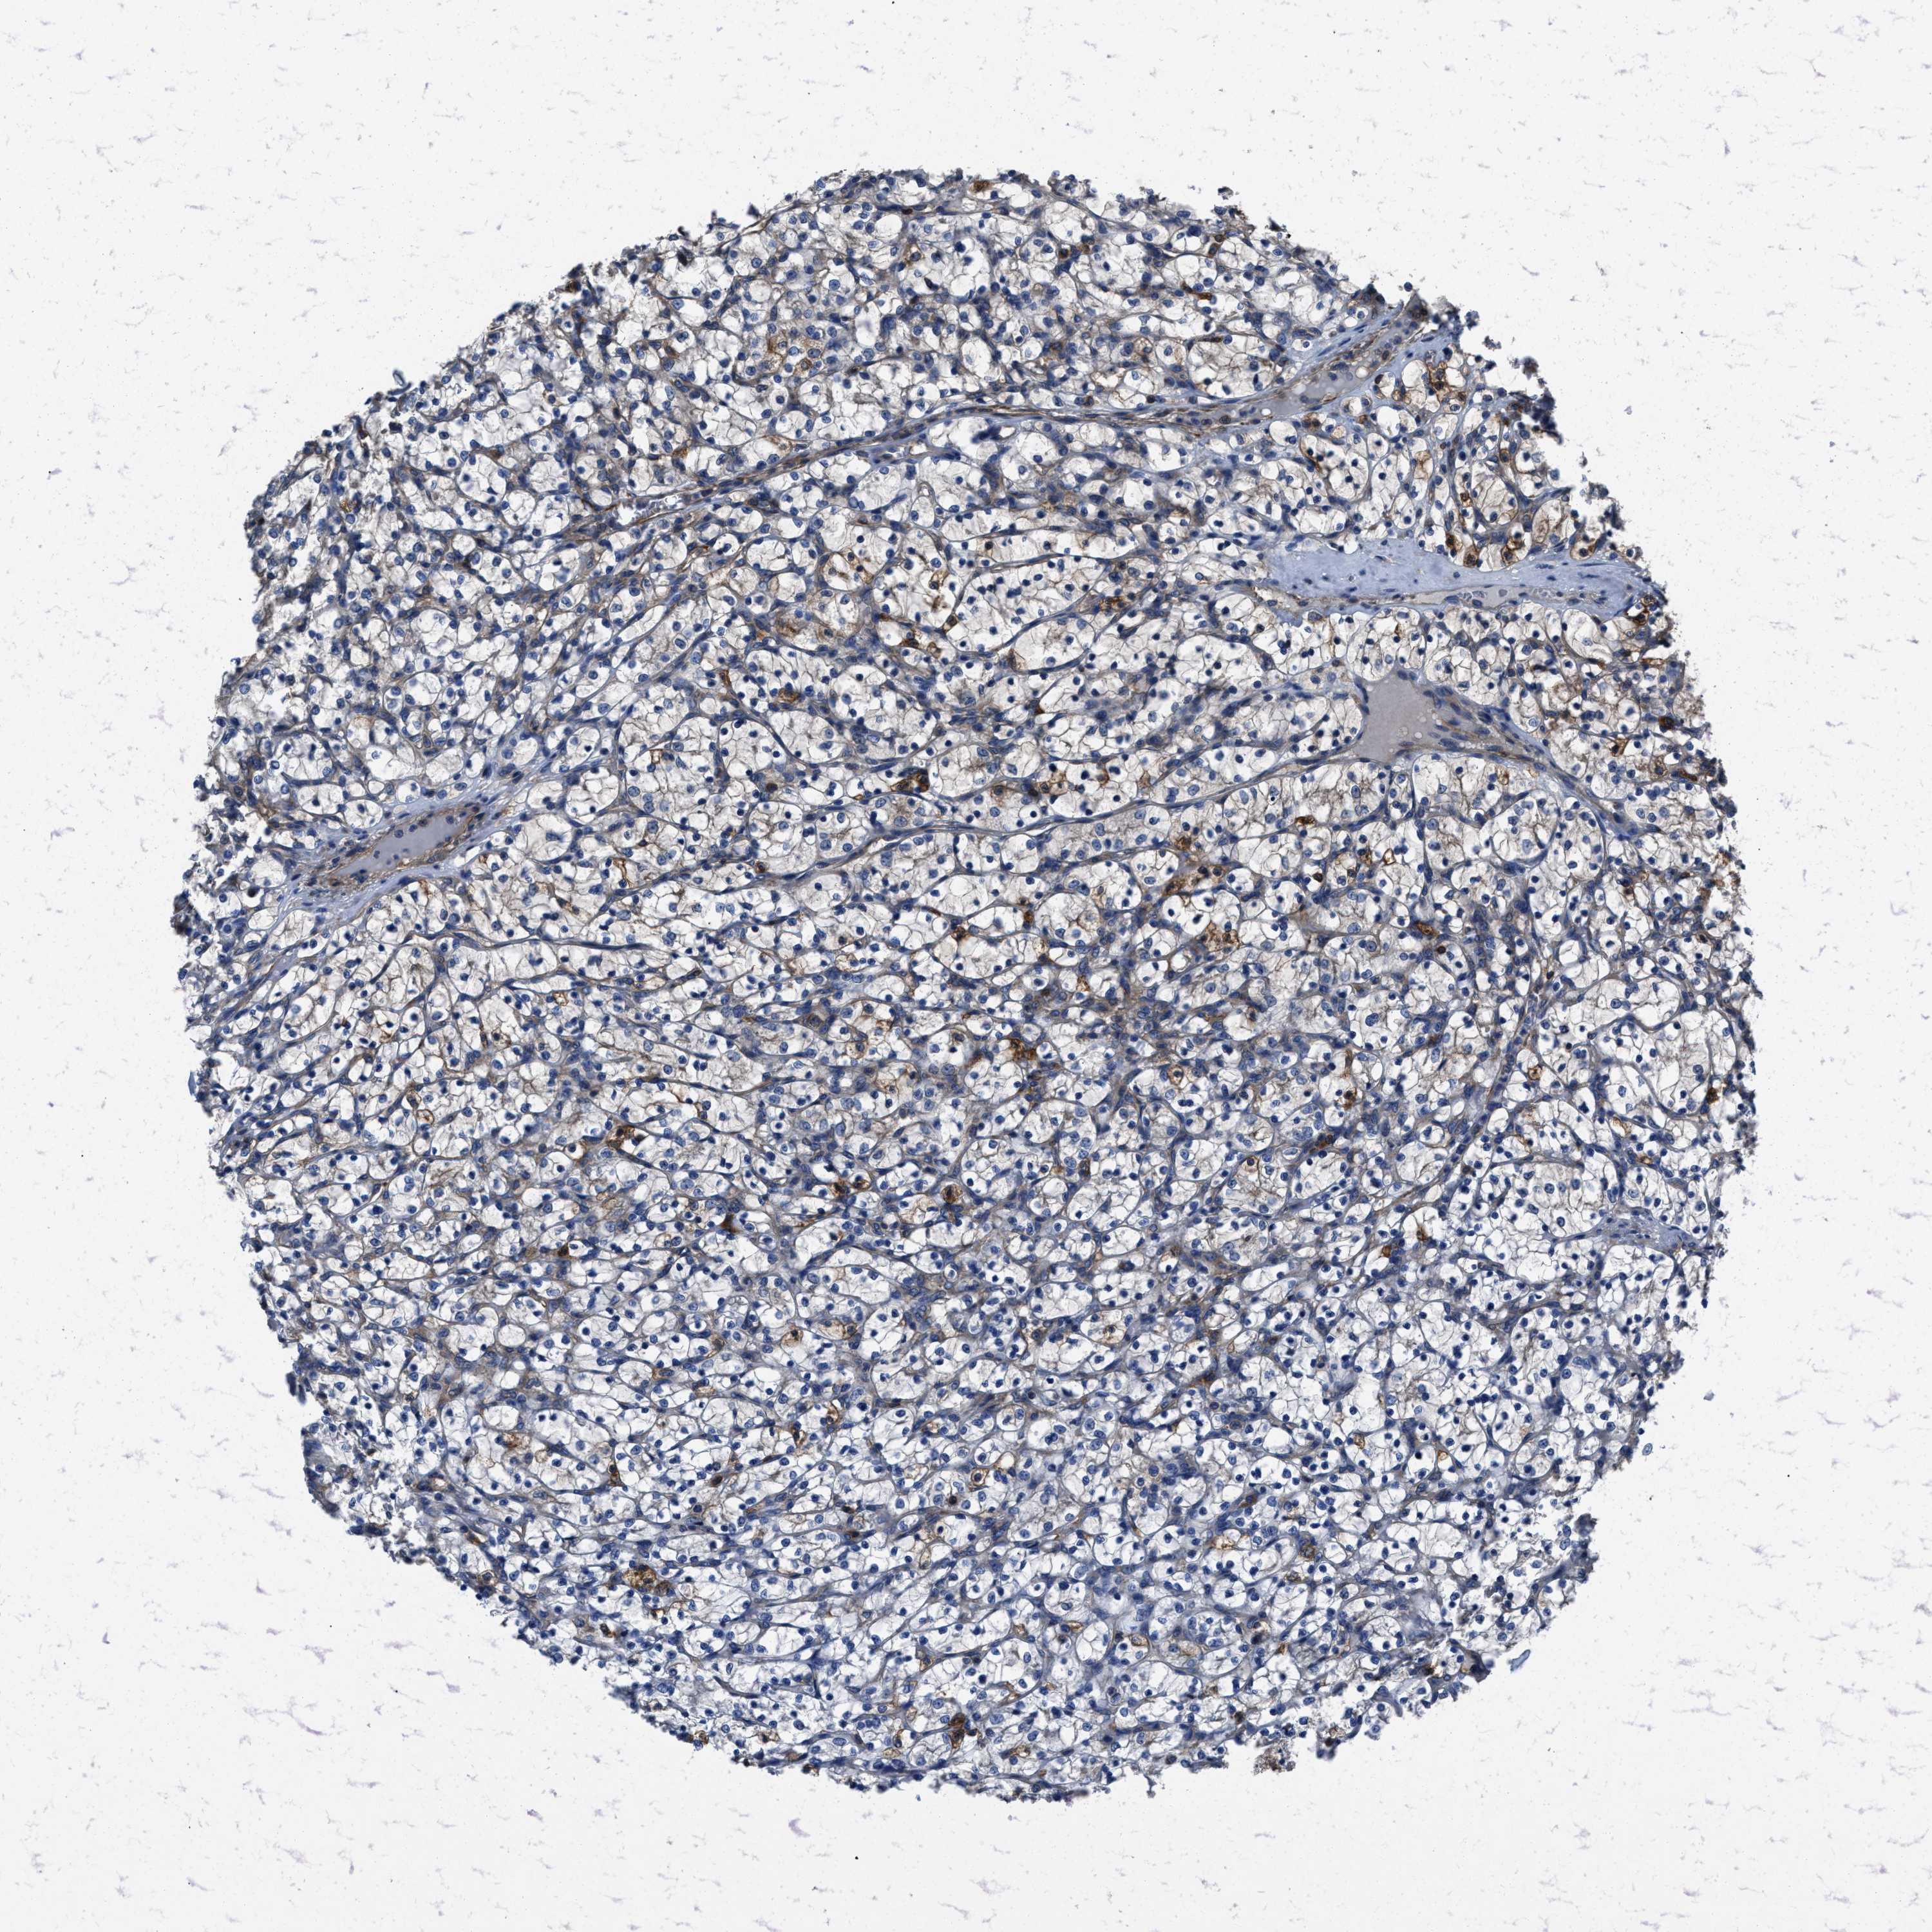

KIDNEY RENAL CLEAR CELL CARCINOMA (TCGA) - Interactive survival scatter ploti

The Survival Scatter plot shows the clinical status (i.e. dead or alive) for all individuals in the patient cohort, based on the same data that underlies the corresponding Kaplan-Meier plots. Patients that are alive at last time for follow-up are shown in blue and patients who have died during the study are shown in red.

The x-axis shows the expression levels (FPKM) of the investigated gene in the tumor tissue at the time of diagnosis. The y-axis shows the follow-up time after diagnosis (years). Both axes are complimented with kernel density curves demonstrating the data density over the axes. The top density plot shows the expression levels (FPKM) distribution among dead (red) and alive patients (blue). The right density plot shows the data density of the survived years of dead patients with high and low expression levels respectively, stratified using the cutoff indicated by the vertical dashed line through the Survival Scatter plot. This cutoff is automatically defined based on the FPKM cutoff that minimizes the p-score. The cutoff can be changed by dragging the vertical line or by entering a cutoff value in the square labeled "Current cut-off".

Under the Survival Scatter plot the p-score landscape (black curve; left axis) is shown together with dead median separation (red curve; right axis). Dead median separation is the difference in median mRNA expression between patients who have died with high and low expression, respectively. It is calculated as follows: median FPKM expression of dead patients with high expression - median FPKM expression of dead patients with low expression. This is intended to aid the user in visually exploring custom cutoffs and the associated p-scores and dead median separation.

Individual patient data is displayed and can be filtered by clicking on one or more of the category buttons on the top of the page. Categories describing expression level and patient information include: high, low, alive, dead, female, male and tumor stages. The scale of the x-axis can be toggled between linear and log-scale by clicking on the "x log" button. Mouse-over function shows TCGA ID, patient information and mRNA expression (FPKM) for each patient.

& Survival analysisi

Kaplan-Meier plots summarize results from analysis of correlation between mRNA expression level and patient survival. Patients were divided based on level of expression into one of the two groups "low" (under cut off) or "high" (over cut off). X-axis shows time for survival (years) and y-axis shows the probability of survival, where 1.0 corresponds to 100 percent.

YARS1 is not prognostic in Kidney Renal Clear Cell Carcinoma (TCGA)

Best expression cut offi

Based on the FPKM value of each gene, patients were classified into two groups and association between prognosis (survival) and gene expression (FPKM) was examined. The best expression cut-off refers the FPKM value that yields maximal difference with regard to survival between the two groups at the lowest log-rank P-value. Best expression cut-off was selected based on survival analysis .

When clicking on this number, the vertical dashed line indicating cut-off, the interactive survival plot, and the Kaplan-Meier curve will be adjusted to show results based on the best expression cut-off.

: 24.39

P scorei

Log-rank P value for Kaplan-Meier plot showing results from analysis of correlation between mRNA expression level and patient survival.

N/A

TCGA RNA samplesi

RNA-seq data is reported as average FPKM (number Fragments Per Kilobase of exon per Million reads), generated by the The Cancer Genome Atlas (TCGA) .

Normal distribution across the dataset is visualized with box plots, shown as median and 25th and 75th percentiles. Points are displayed as outliers if they are above or below 1.5 times the interquartile range. FPKM values of the individual samples are presented next to the box plot.

Average pTPM 33.1

Number of samples 521